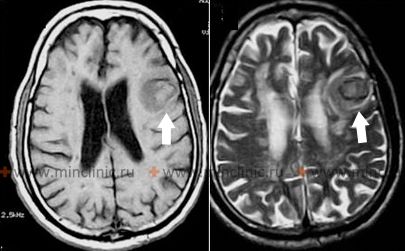

Lobar intracerebral hemorrhage

As hypertension control improves in the population, the relative proportion of intracerebral hemorrhages occurring outside the typical deep hypertensive locations (basal ganglia, thalamus) increases [1]. These hemorrhages, often termed "lobar hemorrhages," typically appear on brain imaging (MRI or CT) as oval or rounded collections of blood primarily located within the subcortical white matter of the cerebral lobes [1, 2]. While chronic hypertension can be a contributing risk factor, especially for Cerebral Amyloid Angiopathy (CAA), it is often *not* the primary underlying cause, and many patients with lobar hemorrhage do not have a history of significant hypertension [1, 3]. Specific underlying structural lesions or conditions are identified in a substantial proportion of cases, including [1, 2]:

CAA is a major cause of spontaneous, often recurrent, lobar hemorrhage in the elderly [3]. Patients with CAA may also exhibit other imaging findings like cerebral microbleeds (predominantly in lobar locations), cortical superficial siderosis, and white matter hyperintensities on MRI [2, 3].